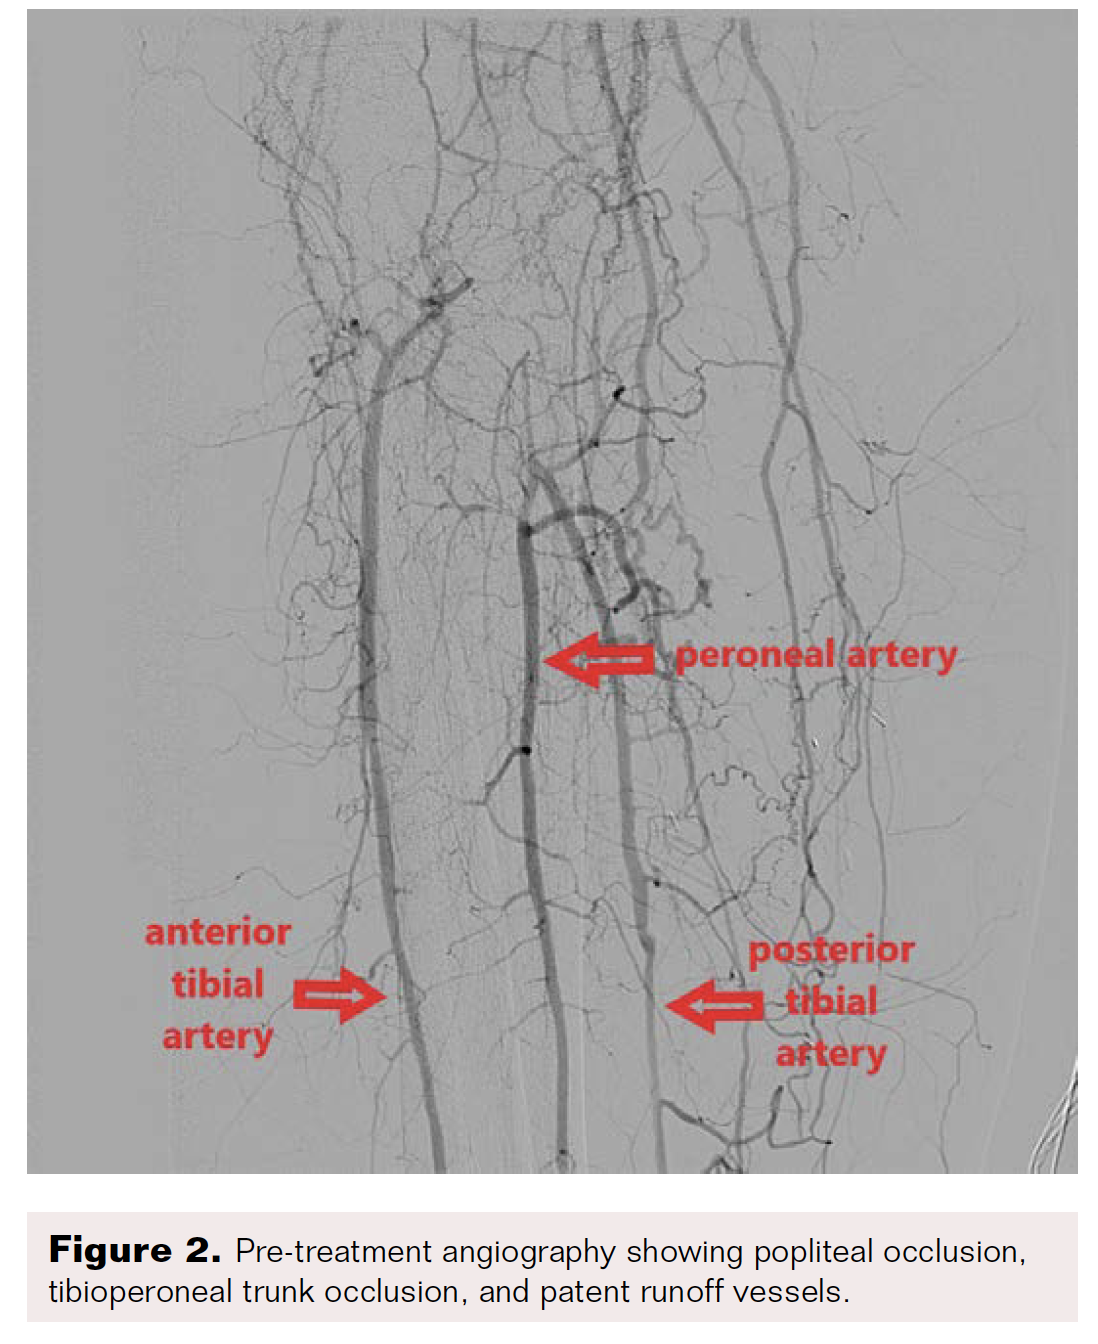

Computed tomography angiography highlighted thrombosis of the femoroposterior tibial bypass and a grade 4 Global Limb Anatomic Staging System femoropopliteal and tibioperoneal trunk chronic total occlusion (CTO). Runoff vessels were patent (Figure 2). Through retrograde posterior tibial puncture, we tried to recanalize the CTO but were not able to get into the common femoral artery (CFA) because the SFA ostium was ligated (Figure 3). We performed a short Dacron prosthetic bypass between the CFA and the proximal part of the SFA (Figure 4), followed by stenting of the whole SFA and the proximal third of the popliteal artery with drug-eluting stents. The distal part of the popliteal artery and the tibioperoneal trunk were treated with balloon angioplasty.